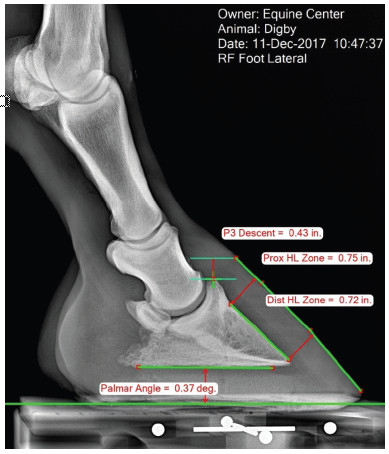

Learn how to take quality radiographs and photographs of the horse's hoof for precise measurements

Utilize Metron software for easy and precise measurements

Calibration in Equine Hoof Imaging

Hoof Image Calibration Article